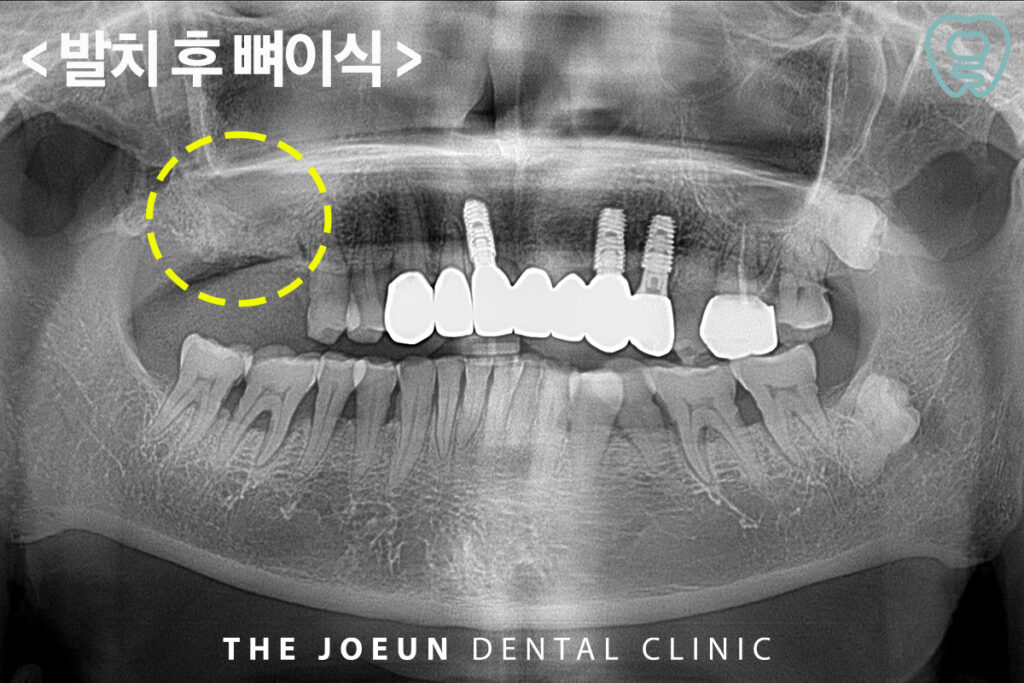

먼저 원인이 되는 어금니를 발치하고 1차적인 뼈이식을 진행하였는데요.

수술에는 자가골, 동종골, 합성골 등 안전성이 입증된 재료만 사용하며 환자 상태와 부위에 따라 최적의 재료를 선택하며 수술 후에는 감염 예방과 이식된 뼈의 안정적 정착을 위해 강창역치과의 정기 검진과 철저한 위생 관리가 요구됩니다. 더불어 환자의 회복 상태를 지속적으로 확인하고 필요 시 신속히 대응하는 사후 관리 과정 역시 성공적인 치료에 중요한 요소가 될 것입니다.